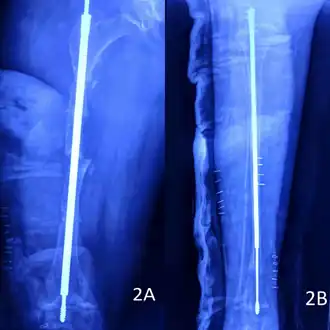

Rodding

Metal rods can be surgically inserted in the long bones to improve strength, a procedure developed by Harold A. Sofield when he was Chief of Staff at Chicago's Shriners Hospitals for Children, a hospital that offers orthopedic care and surgery to children regardless of their family's ability to pay.[115] Large numbers of children with OI came to Shriners, and Sofield experimented with various methods to strengthen their bones.[116] In 1959, with Edward A. Millar [sic], Sofield wrote a seminal article describing a three-part surgery that seemed radical at the time: precisely breaking the bones ("fragmentation"), putting the resulting bone fragments in a straight line ("realignment"), then placing metal rods into the intramedullary canals of the long bones to stabilize and strengthen them ("rod fixation").[117] His treatment proved useful for increasing the mobility of people with OI, and it has been adopted throughout the world—it became standard surgical treatment for severe OI by 1979, in which year David Sillence found that ≈2⁄3 of the patients he surveyed with OI type III had undergone at least one rodding surgery.[42]: 108

Rodding surgery is often done with the hope that it will offer a path to ambulation, walking, to patients with moderate or severe OI. A 2020 review in The Journal of Bone and Joint Surgery (JB&JS) found it remains broadly popular: ≈2⁄3 of people with OI types III and IV (severe OI) have undergone some form of rodding surgery in their lives, at a mean age of 4+1⁄10 and 7+1⁄2 years respectively;[25]: Table I one possible explanation for a tendency towards earlier intervention in type III is that one half of affected children could not walk at all without the surgery, as their limbs were more bowed, so surgery was sought sooner.[25]

In those with type III OI who had undergone rodding surgery, 79.5% had the femurs and tibias of both legs rodded.[25]: Table I The most common form of rods used are intramedullary (IM) rods, some of which, such as the Fassier–Duval IM rod, are telescoping, meaning that they are designed to grow as the child grows, in an attempt to avoid the necessity of revision surgeries.[118] Telescoping IM rods are widely used,[119] and the common Fassier–Duval IM rod is designed to be used to rod the femur, tibia, and humerus.[120]: 1 The surgery involves breaking the long bones in between one and three (or more)[119]: Figure 4 places, then fixing the rod alongside the bone to keep it straight.[120]: 11

While telescoping IM rods are intended to grow along with both the femur and tibia in developing children; surgeons have a preference to use non-telescoping IM rods, such as Rush rods, in the tibia, which grows less comparatively—the JB&JS review found that while 69.7% of femurs were treated with telescoping IM rods, only 36.9% of tibiae were.[25]: Table IV

While the review in the JB&JS was able to correlate receiving rodding surgery with greater mobility across all types of OI, in patients with type IV, the surgery did not decrease the incidence of broken bones as compared to non-rodded patients—while type IV patients with rodded tibiae experienced 0.93 tibia fractures per year, patients with natural tibiae experienced only 0.81. However, in patients with type III, rodding surgery decreased the average number of tibia fractures per year from 0.84 to 0.57.[25]: Table V